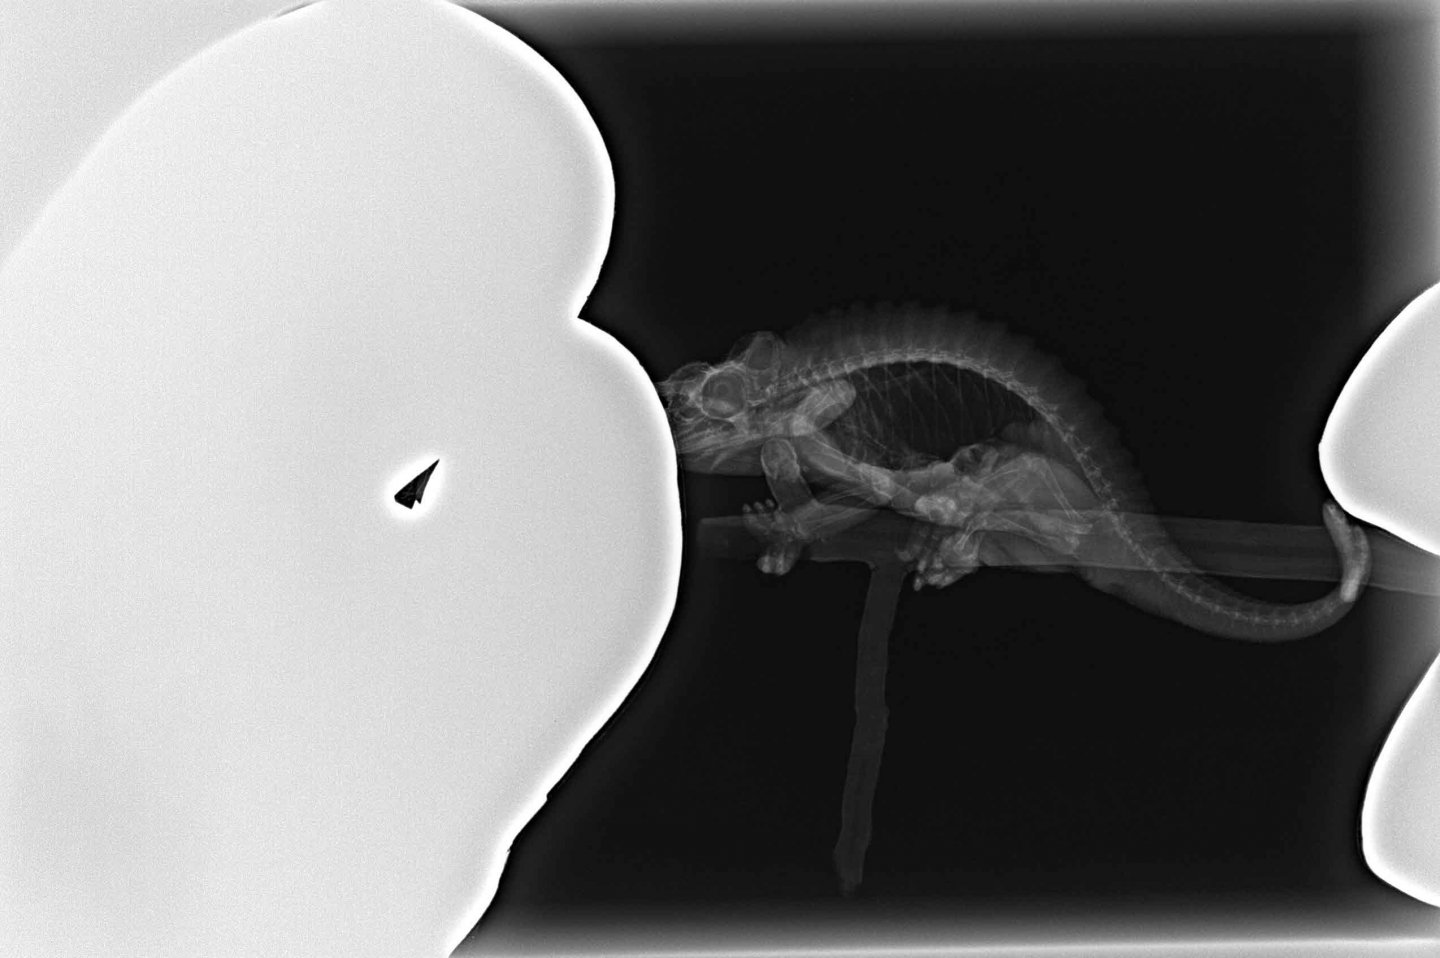

Nothing obvious on his radiographs. No evidence of old or new fractures or previous MBD, bone density looks okay. Lung field looks good where not overlapped by legs. Stomach is empty. Kidney and testes silhouette looks pretty normal. Colon area looks full but unfortunately a little hard to evaluate much more than that because the back legs are in the way. So nothing obvious on this diagnostic. If husbandry is good then bloodwork would probably be the next step.

Positioning reptiles, especially chameleons, for X-rays so they're flat and the legs are out of the way is challenging. The best method I've found is a little bit of lizard bondage honestly - you have the wrap their little legs and tape them down. It sounds a little mean but it doesn't hurt them and when done fast (and I'm super speedy) they don't seem terribly stressed by it. Here's a beardie demonstrating ;)

Some X-ray machines can rotate so they shoot horizontally so a chameleon just sitting on a perch is usually well positioned enough to not need restraint. My machine unfortunately does not have this capability. Dr. Mader's does of course.